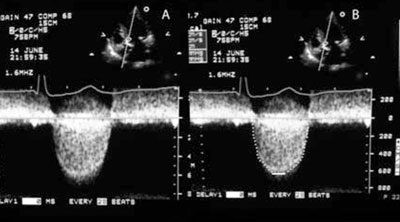

A todos se les realizó un ED siguiendo las recomendaciones de la Sociedad Americana de Ecocardiografía9,10,13. El diámetro de la cámara de salida del ventrículo izquierdo (CSVI) se midió con zoom en la mesosístole, de borde interno a borde interno, en paralelo y próximo al plano valvular aórtico. Para medir la velocidad de CSVI se utilizó el Doppler pulsado (DP) en el enfoque apical. Se ubicó la muestra de volumen próxima al lado ventricular de la válvula a una altura que permitiese el registro de un flujo laminar. La VMáx de la válvula aórtica con DC se midió sobre el pico máximo de la curva, densa y bien dibujada, sin considerar ruidos y señales lineales finas. Con el trazado de la integral velocidad-tiempo sobre el borde externo de la señal densa se cuantificó el GM (Figura 1). De forma rutinaria se estudiaron las ventanas apical, PED con Pedof (borde derecho del esternón en diferentes espacios intercostales con el paciente en decúbito lateral derecho) y subxifoidea. Se utilizaron filtros de pared altos y ganancias de DC bajas para definir nítidamente las curvas Doppler que se desplegaron en la pantalla a velocidades de barrido de 100 mm/s. Para la obtención de la curva se tomó en cuenta la nitidez de los bordes, la intensidad de la señal y las características acústicas.

Figura 1 Registro con DC desde el enfoque apical. A: Registro sobre el que se realizan las mediciones. B: La VMáx se mide sobre el pico máximo de la curva, densa y bien dibujada, sin considerar los ruidos y las señales lineales finas. El trazado de la integral velocidad-tiempo se realiza sobre el borde externo de la envolvente, densa y bien definida.